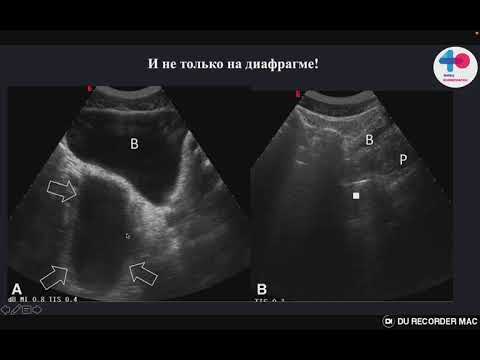

eFAST протокол ошибки и подводные камни метода